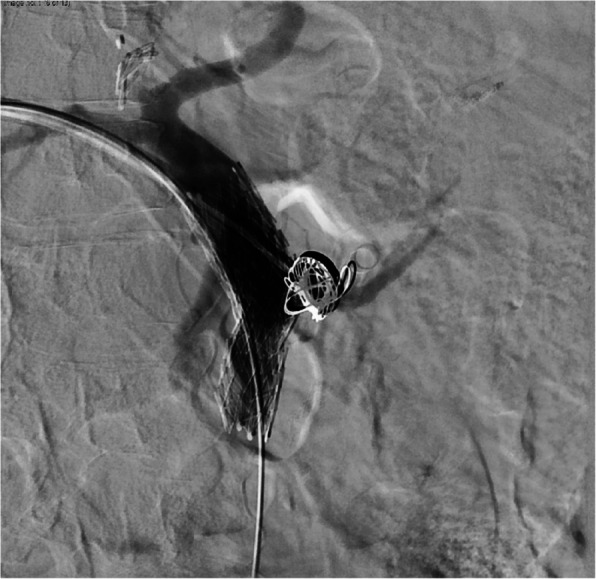

This case describes the endovascular treatment of a 55-year old female with a ruptured portal vein pseudoaneurysm secondary to a large stomach ulcer resulting in massive active hemorrhage into the adjacent stomach. This patient presented with persistent hypotension secondary to chronic GI blood loss and simultaneous septic shock. After an abrupt drop in blood pressure, the patient arrived in the angiography suite where the ruptured pseudoaneurysm was apparent on portal venogram. Emergent stent assisted coil embolization was performed to stabilize the patient and treat the portal vein pseudoaneurysm. To our knowledge, this case presents the only portal vein pseudoaneurysm secondary to a gastric ulcer.Level of Evidence Level 4, Case-report.

Abstract Image